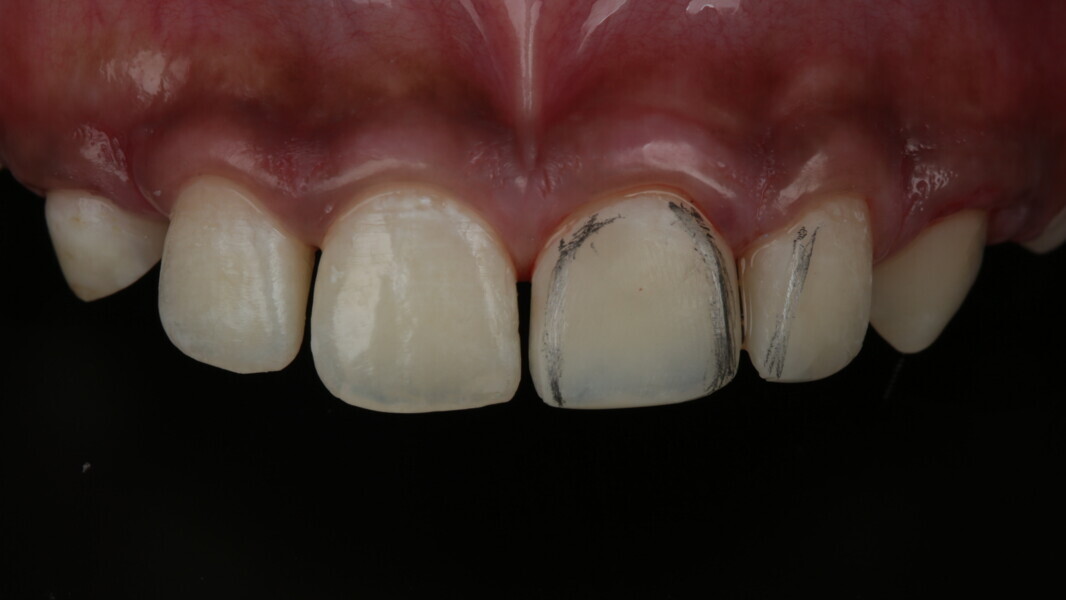

A 10-year-old male patient reported with a complaint of trauma to the upper left central and lateral incisors, involving the enamel and dentin. Direct composite was used in multi-layers and the smile was restored. This article explains detailed steps in the polychromatic layering technique with special emphasis on the finishing and polishing protocol. 3M Espe Filtex Z350 Xt was used with a universal bonding agent.

Fig 1-7: Evaluation and mock up